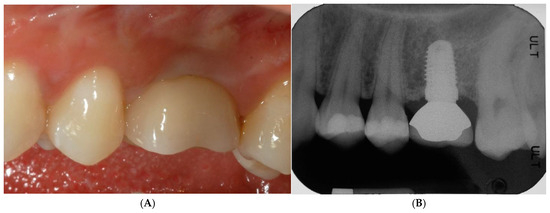

After implant insertion (Figure 7D), a healing abutment was immediately connected (Figure 7E) for transmucosal healing, avoiding additional surgery. After a 2-month healing time (Figure 7F), a provisional restoration was applied for progressive loading. At 6 months after implant insertion, a definitive porcelain-fused-to-metal crown was cemented (Figure 8A–C).

Figure 8.

Provisional restoration was applied for progressive loading. At 6 months after implant insertion, a definitive porcelain-fused-to-metal crown was cemented (A–C).

This GBR procedure was effective for the reconstruction of the horizontal defect, and the bone underneath the TR-dPTFE membrane appeared well mineralized after a healing period of 10 months. The implant was inserted in well-matured and vascularized bone and achieved primary stability very easily. No additional ridge augmentation was required for implant placement. Regenerated bone was found to be uniform across the defect and was hard and well integrated. The patient was very satisfied with the aesthetic result of the prosthetic rehabilitation and the improved masticatory function. She was monitored at least twice a year, when she returned for professional hygiene sessions. There were no problems of peri-implantitis, unscrewing of the implant abutment screw or soft tissue recession. The 5-year clinical and radiographic follow-up after functional prosthetic loading showed the augmented hard and soft tissues well maintained, with no marginal bone loss around the implant and a bone density within the limits (Figure 9A,B).

Figure 9.

5-year clinical (A) and radiographic (B) follow-up after functional prosthetic loading showed augmented hard and soft tissues, which were well maintained.